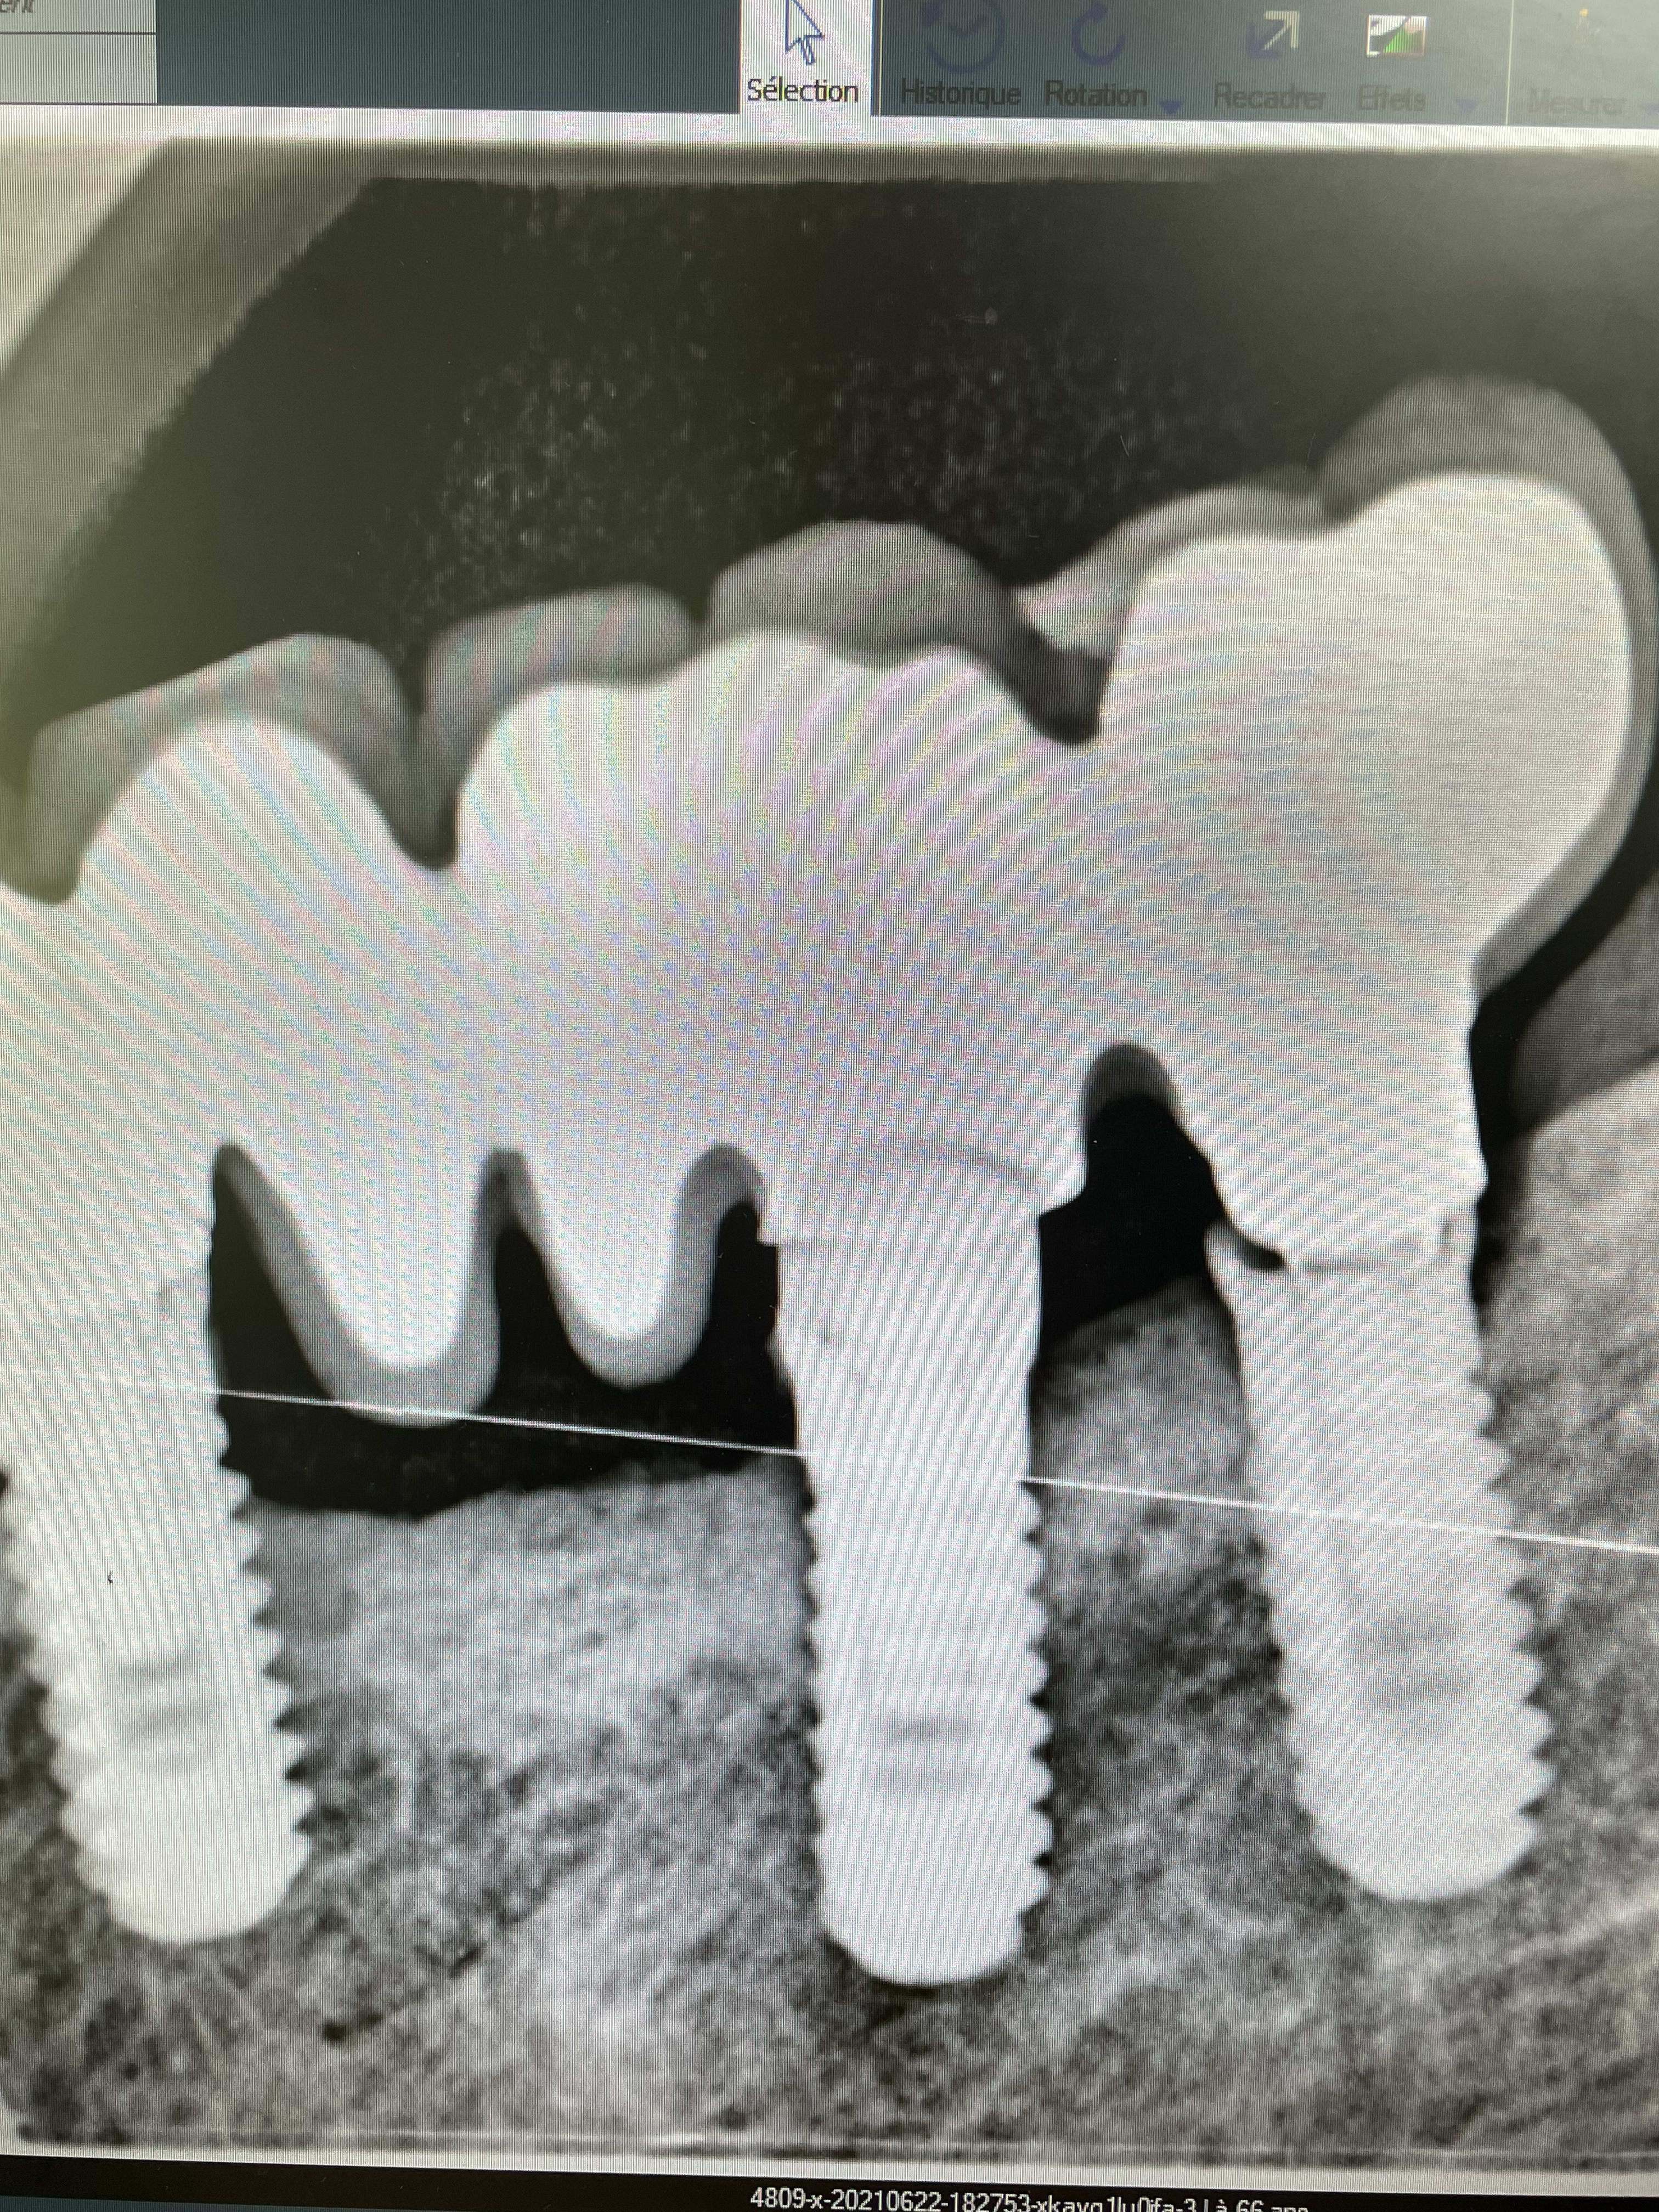

Autre cas à reprendre… implants posés en 1994. Ça ressemble à de l’onb…. Une idée de la compatibilité éventuelle avec le repreneur idi ?

Pas de bras pas de chocolat

Pas de bonnes images, pas d'identification